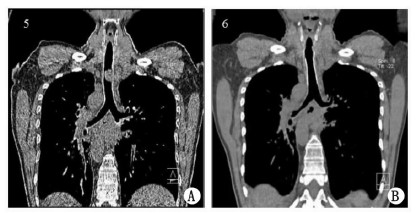

例2 患者男性,49 岁,因“确诊食管癌1年余,呼吸困难进行性加重1周”于2011年1月17 日入住邵逸夫医院。患者诊断食管癌1年余,曾行放疗1疗程,化疗7疗程。1周前出现气急进行性加重。体格检查:端坐呼吸,吸气时可见明显的三凹征,双肺双相干啰音,以胸骨柄处最明显。胸部CT:全内脏反位,气管中段腔内肿块,长约3 cm,管腔明显狭窄(图 2A)。入院后第2天患者呼吸困难进一步加重,面罩吸氧8 L/min下SpO2在 80%~85%,次日尝试支气管镜检查,患者根本无法耐受,气管镜连声门也进不了。遂选择ECMO支持下经支气管镜行气管支架植入术。采用股静脉-股动脉(V-A)模式,丙泊酚静脉麻醉镇静,循环系统预充:新鲜血浆100 mL,R-L液400 mL,肝素2 mg/kg,转流中监测MAP、SpO2。纤维支气管镜见气管中段管腔外压性狭窄伴腔内新生物,管腔基本堵塞,予顺利植入气管支架,镜下见原病变处管腔较前明显通畅。术后患者咳嗽气急症状明显缓解,1 d后复查胸部CT示:气管管腔通畅,支架位置良好(图 2B)。复查支气管镜:气管中段支架已完全张开,气管管腔通畅。随访1月无明显气急。

图 2 A:术前胸部CT平扫加重建示,胸廓入口处T2椎体水平食管左侧肿块,侵犯前方并向气管内生长,气管腔部分狭窄。B:术后第3天胸部CT平扫加重建示,气管内占位已未见,气管支架植入,气管腔通畅,未见明显狭窄或新生物。

例3 患者男性,60 岁,因“进食哽咽感1月,加重伴气急3 d”入院。胸部CT:气管中段管腔内肿块,气管狭窄,后纵膈肿物。予以吸氧等对症支持治疗,气急症状进行性加重。体格检查:呼吸急促,双肺双相干啰音。入院后予以高流量面罩吸氧下SpO2在 90% 左右。遂行ECMO下经支气管镜气管支架植入术,操作步骤同前,术后患者气急缓解。术后3 d行电子胃镜检查:进镜至食道距门齿18 cm处受阻,近全周粘膜呈不规则结节样隆起新生物,被覆灰白坏死苔,质脆易出血,伴该段食管狭窄,无法继续进镜,取活检3块。活检病理:食管癌侵犯气管(鳞癌)。予以对症支持治疗,呼吸平稳,有吞咽困难,出院后随访一月无明显气急。